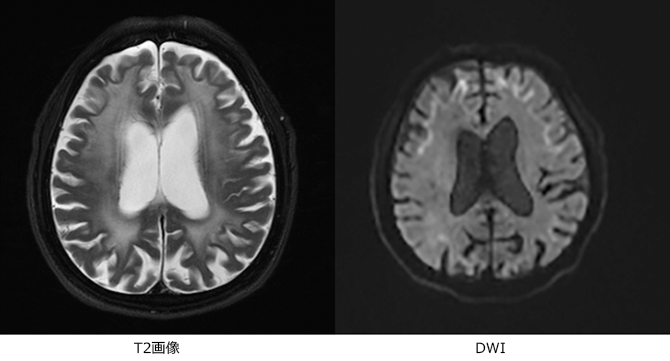

NIIDの患者さんでは、特に物忘れの症状のある方では、脳のMRIを撮影すると、白質脳症(図2の様にMRI T2画像で脳の深部が白く写ること)が認められ、拡散強調画像(DWI)という特殊な条件で撮影すると、線状の高信号が認められることがあります(図2)。

- 図2:NIIDの頭部MRI所見